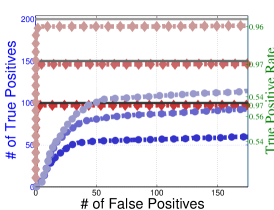

To understand the performance of this standard method, we present a small preview of our simulation study discussed later in Section 4. Briefly, we assume that each subject graph in group follows a small-world structure on nodes; in group , there are in addition 150 differential edges, meaning that and for all differential edges, . We generate data according to this model with time points and subjects in each group. Figure 1 illustrates the results of this standard approach as well as our new procedure, , which we will introduce later in Section 3. Part (a) gives ROC curves for the number of false positives verses true positives as each sequential test is rejected; parts (b) and (c) give the adjacency confusion matrix illustrating where the true and false positive as well as false negative edges are detected in the graph structure.

Our motivating simulation shows that the standard approach performs terribly in terms of both error control and statistical power. While the magnitude of the poor performance of this approach may seem astonishing, the poor performance should come as no surprise: The inferential procedure (e.g. test statistics) of the standard approach assume a one-level model that would be appropriate when the subject graphs are fixed and known or directly observed quantities. When these subject networks are unobserved, however, and must be estimated from finite data, these one-level test statistics are incorrect for our two-level problem. Specifically for two-level problems, the variance of parameters estimated by incorrectly assuming a one-level models is underestimated. For our problem, the extra source of variability arises from the graph selection procedure; we discuss challenges associated with this subsequently in Section 2.2. Incorrect variance estimates, however, are not the only problem with the standard approach: A more subtle problem arises from the fact that the proclivities of graph selection procedures for the Gaussian graphical model lead to biased estimates of the edge proportions, . As discussed in Section 2.3 and seen in Fig 1, graph selection false positives and false negatives do not occur at random throughout the network structure, leading to biased group level estimates.

Hence, the first term represents variability across subjects in group and the second term represents the variability associated with the selection procedure within subject , a quantity that we assume to be constant across subjects in each group . Consider now what happens if our true model follows this two-level Beta-Binomial model, but as with the standard approach, we use a one-level Binomial model and associated two-sample test statistic. The variance is thus underestimated and the test statistic is overoptimistic. Then, when inference is conducted for the population mean , using the incorrect Binomial model leads to inflated Type I error rates; this behavior has been well-documented (Weil, 1970; Liang and Hanfelt, 1994). Hence, failure to use the correct two-level model which accounts for the two levels of network variability partially explains the high error rates of the standard procedure observed in Figure 1.

In Figure 4 and Table 1, we present our main simulation results comparing to the two variations of our method and the standard approach for three network structures and Case I and II type differential edges. First for Figure 4, we report results in terms of operating characteristics averaged across 50 replicates with the number of true positives (y-axis) plotted against the number of false positives (x-axis) for each test statistic, rejected sequentially from largest to smallest in absolute magnitude. Overall, all of our methods and particularly yield substantial improvements over the standard approach in all scenarios.

Notice that both and =(RS,RP) share similar orderings of test statistics, and consequently similar ROC curves. Overall, methods that include random penalization yield major improvements in statistical power over those that do not. This indicates that the second popPSI challenge outlined in Section 2.3 is a significant contributor to the poor performance of the standard method. Recall our discussion of how graph selection errors at the subject stage occur non-randomly and hence bias our group-level estimates of . Our results empirically demonstrate that random penalization dramatically improves these biases, leading to less bias in our test statistics and hence improvements in both Type I and Type II error rates. Furthermore, in Case II scenarios where selection errors are moderate, the performance gap between any method containing over reduces compared to Case I scenarios where selection errors are more severe. Thus, the benefits of random penalization are greater when selection errors are more abundant. Confusion adjacency matrices illustrating the location of inferential errors for our methods shown in the supplemental materials also indicate that random penalization improves graph selection in cases where there are larger correlations between differential edges and common edges. Similar results hold for our high-dimensional study presented in the supplemental material.

Table 1, which accompanies Figure 4, gives the empirical true positive and false discovery rates (FDR) averaged over 50 simulation replicates when the Benjamini-Yekutieli (Benjamini and Yekutieli, 2001) procedure controlling the FDR at 10% is used to determine the number of tests to reject. First, notice that the observed false discovery proportion (FDP) of our procedure is not 10% on average, indicating that our method does not fully control the FDR. This occurs because we specifically simulate difficult and realistic fMRI scenarios with graph structures that severely violate irrepresentable-type conditions. In situations (not shown) where irrepresentable-type conditions are met that ensure graph selection consistency, our procedure as well as the standard method correctly control the FDR. As discussed in Section 2.3, in situations where graph selection errors occur with high probability, it is likely impossible to provably control the FDR, consistent with our empirical results. Yet even though does not fully control the FDR, our error rates are dramatically improved over the standard approach and other variations of our procedure.

Also in Table 1, observe that (RS,RP), which had similarly ordered test statistics to , has dramatically worse Type I error rates that do not come close to controlling the FDR. While (RS,RE) also does not control the FDR, the error rates are much improved over (RS,RP). These results demonstrate that using two-level models with the correct random effects test statistics are crucial to Type I error control. Recall from Section 2.2, that using the one-level Binomial model leads to an under-estimation of the variance term which in turn inflates test statistics and leads to an increase in false positives. Note also that the estimated FDP of is still a major improvement over that of (RS,RE). This occurs as the problem of graph selection errors induces both Type I and Type II errors. Hence, these results demonstrate the necessity of all three of our ingredients. Finally, observe that our error rates in Case II scenarios are better than those for Case I scenarios, again indicating that differential edges that are highly correlated with non-edges and common edges pose particular challenges for our popPSI problem. These results are also corroborated in our high-dimensional study presented in the supplemental materials.

Lastly, in Figure 5, we study the effect of letting the network structure vary across subjects by decreasing the differential group edge probability, . Our method continues to perform well for . However, when the differential edge probability drops further to , we see that both and the standard approach have greatly reduced statistical power, as one would expect. Despite this, continues to outperform the standard approach.